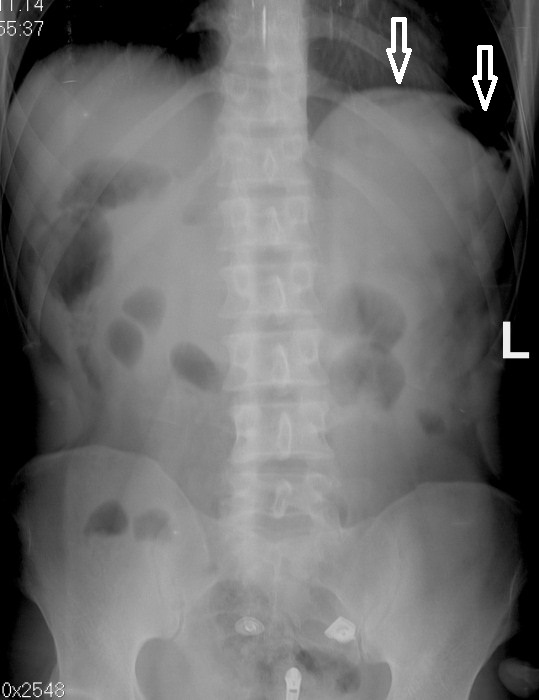

Необычные находки: инородные тела на рентгенограмме брюшной полости